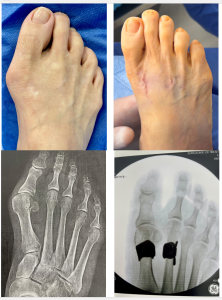

The HyperFlex™️ innovative bunion surgery corrects any level of bunion, from mild to severe, and can be completed in as little as 20-30 minutes with most patients putting weight on their feet immediately afterward. As seen in before-and-after X-rays and photos, the results are instant — bunions are reduced without shaving or removing bone tissue, and only a small scar is left on the top of the foot.

Read our patients’ stories below and see the results for yourself!